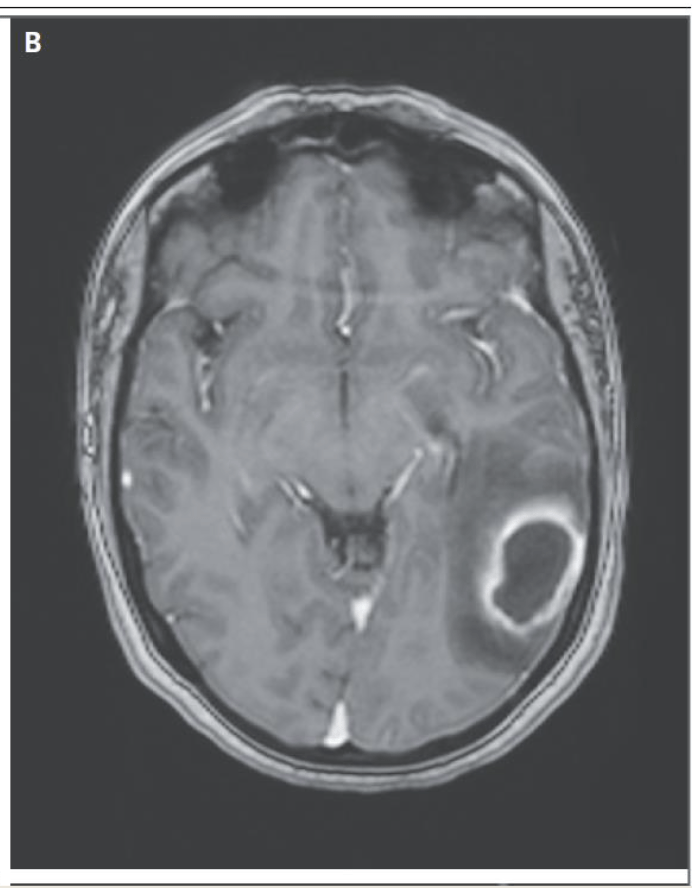

Bacterial infection that can present as subacute purulent skin lesions, lung masses, brain masses, especially in immunocompromised patients

What is Nocardia